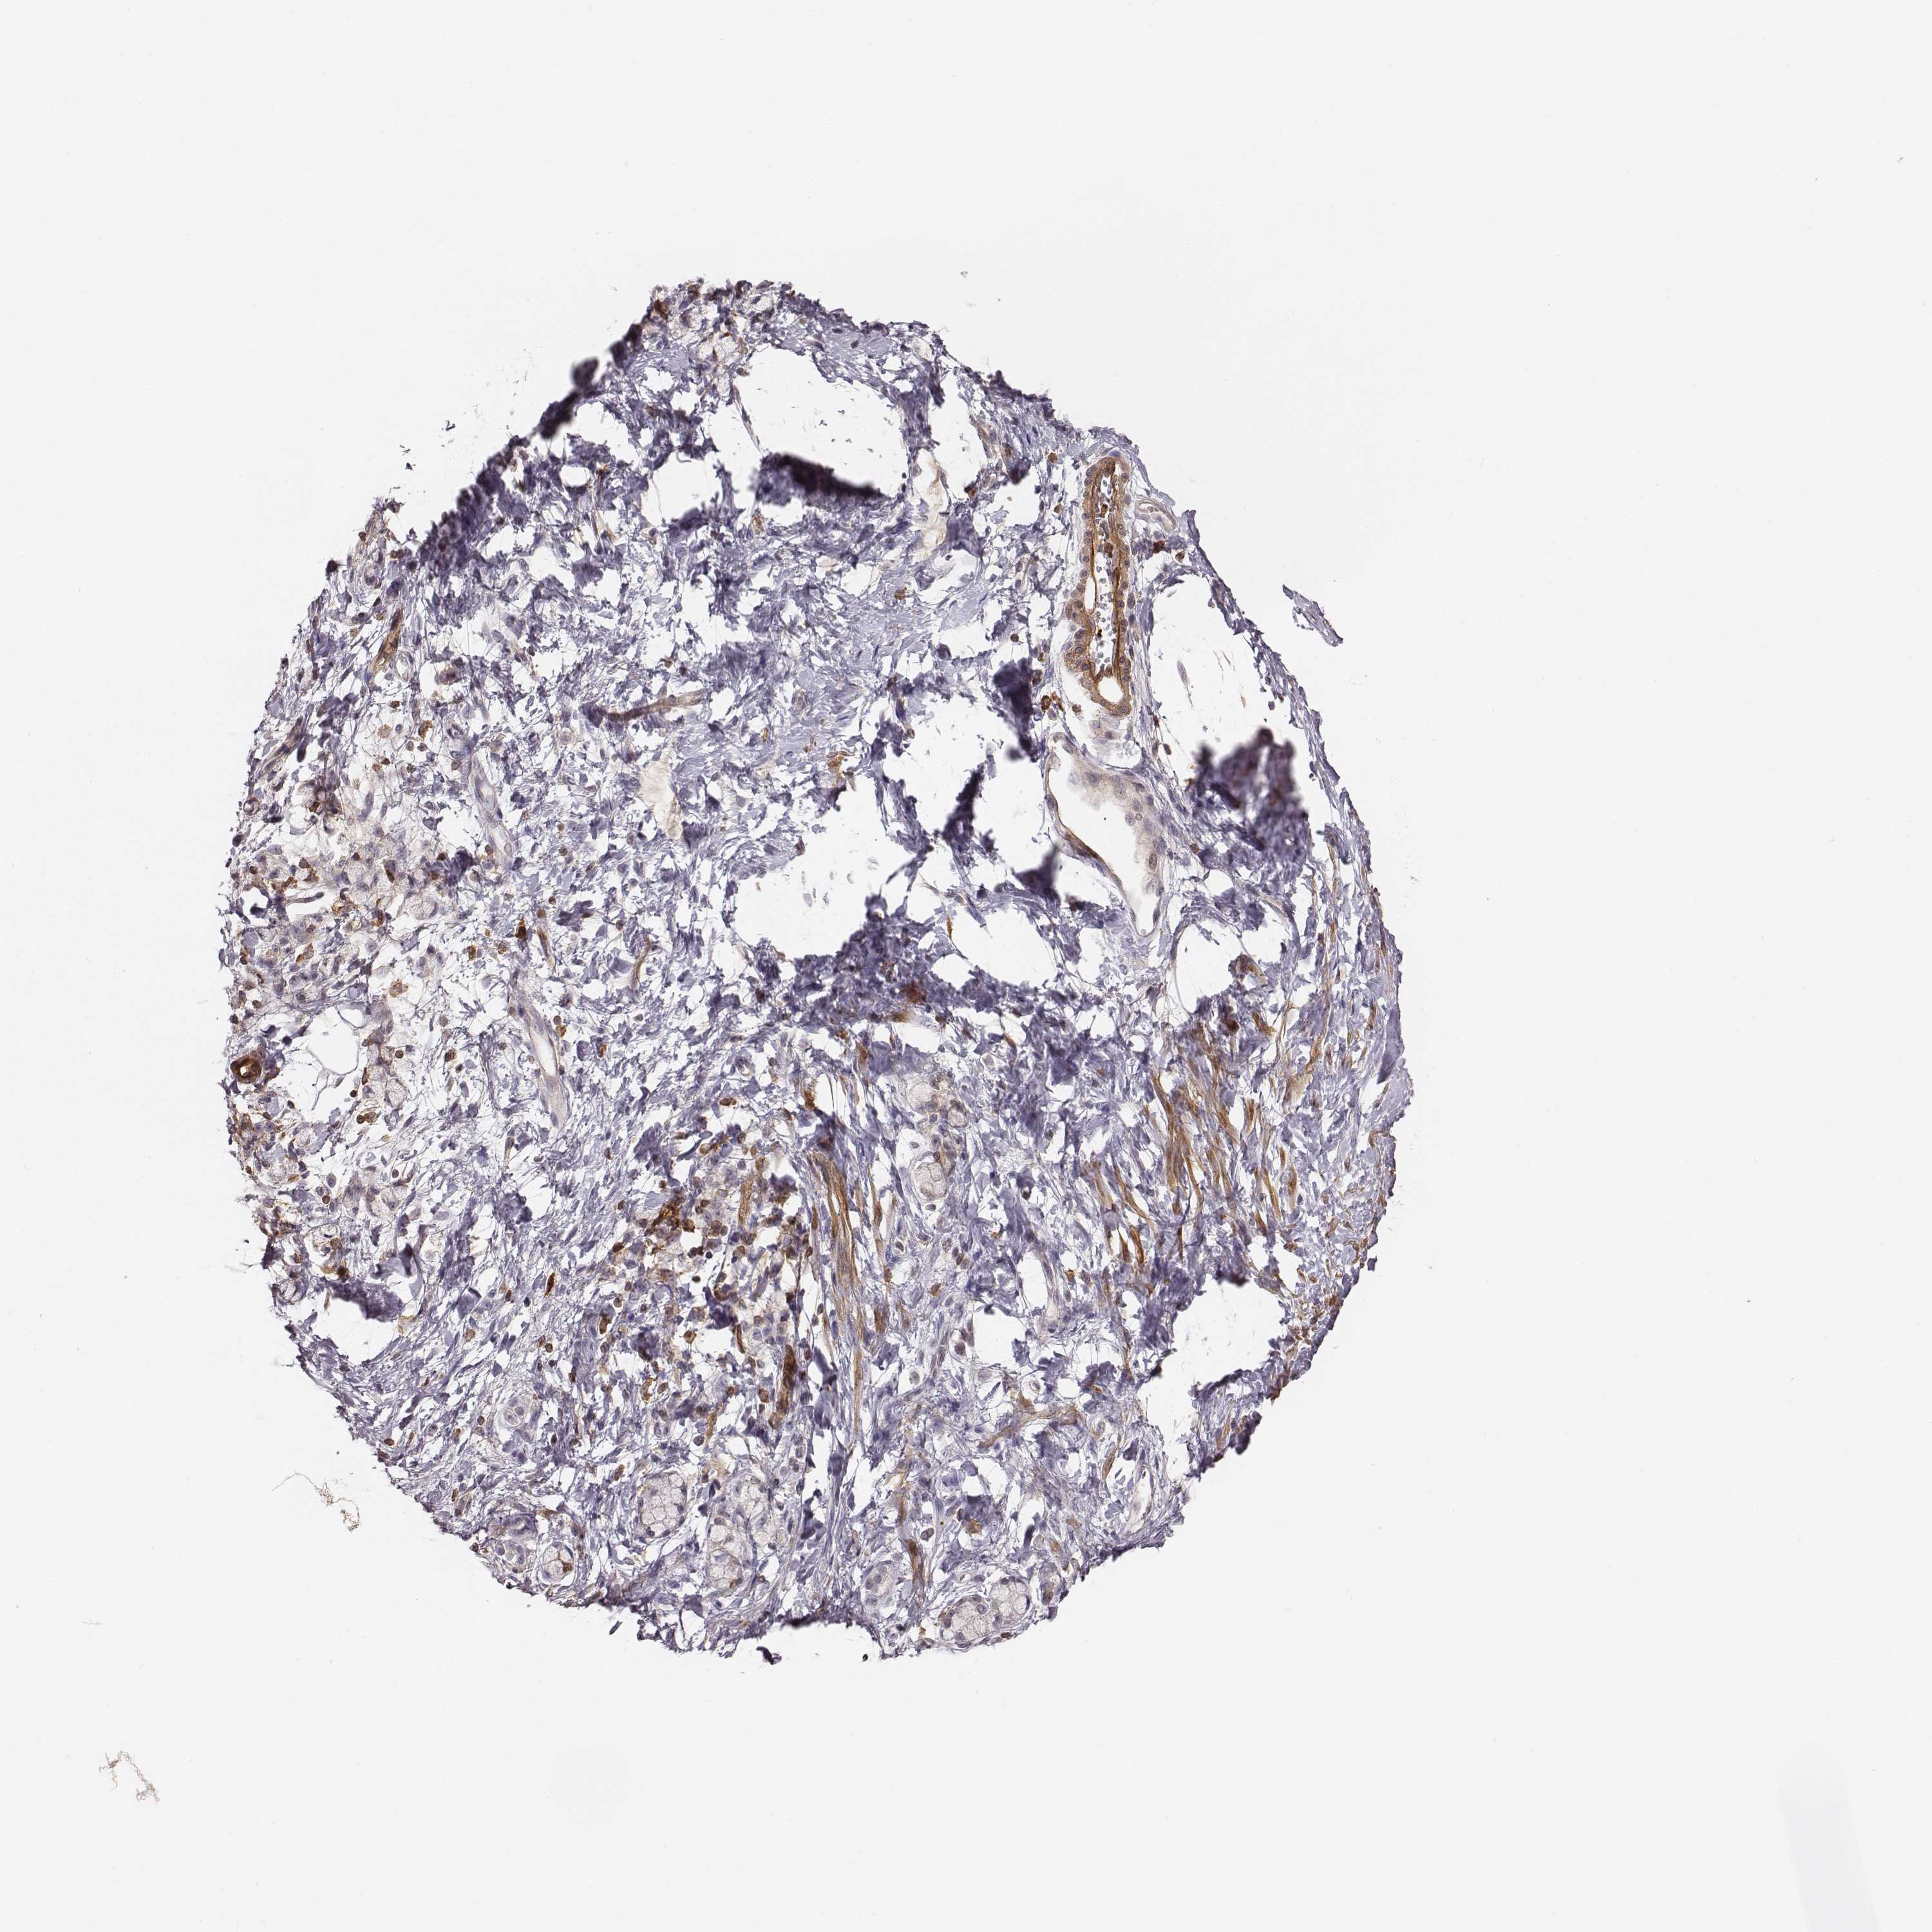

STOMACH CANCER - Protein expressioni

A mouse-over function shows sample information and annotation data. Click on an image to view it in a full screen mode. Samples can be filtered based on level of antibody staining by selecting one or several of the following categories: high, medium, low and not detected. The assay and annotation is described here.

Note that samples used for immunohistochemistry by the Human Protein Atlas do not correspond to samples in the TCGA dataset.

Antibody stainingi

Antibody staining in the annotated cell types in the current human tissue is reported as not detected, low, medium, or high, based on conventional immunohistochemistry profiling in selected tissues. This score is based on the combination of the staining intensity and fraction of stained cells.

Each image is clickable and will lead to virtual microscopy that enables deeper exploration of all samples and also displays staining intensity scores, fraction scores and subcellular localization as well as patient and tissue information for each sample.

Antibody CAB009321

Adenocarcinoma, NOS

Adenocarcinoma, High grade